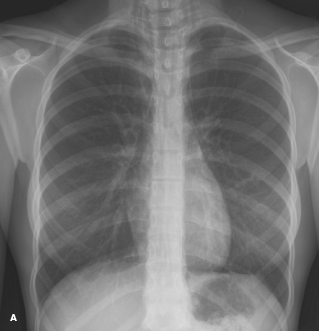

spontaneous pneumomediastinum

Lisa M. Clewner, MD

<p><img src="/sites/default/files/transfer/1202CFP_PCPneumo_A_thumb.jpg" width="87" height="90" style="float: left; margin:...